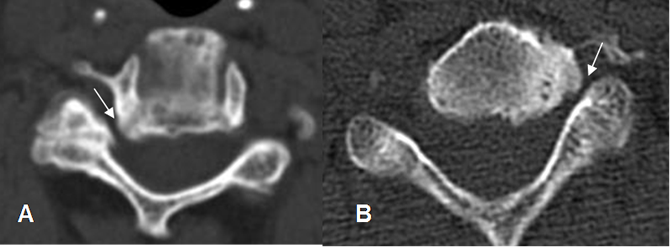

Fig 56. Canal estrecho lateral.

A y B: TAC axial cervical. Hipertrofia de articulaciones uncovertebrales e interfacetarias, que disminuyen la amplitud del agujero de conjunción.

Fig 57. Canal estrecho lateral.

A: Rx oblicua cervical. Disminución en la amplitud del agujero de conjunción.

B: TAC axial. Presencia de osteofito, que ocasiona estenosis del receso lateral.